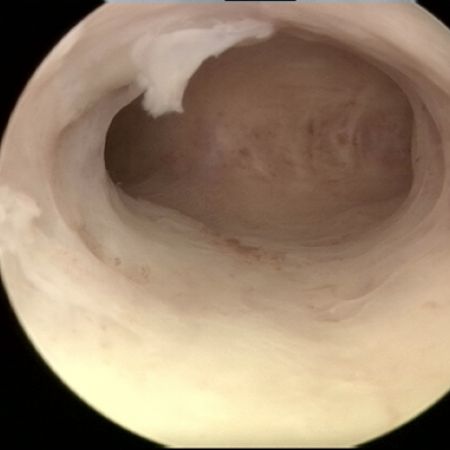

3-D ultrasound and hysteroscopy are excellent methods to evaluate women with IUD problems.

2-D ultrasound examination is often not adequate to detect the position of the transverse in the uterine cavity